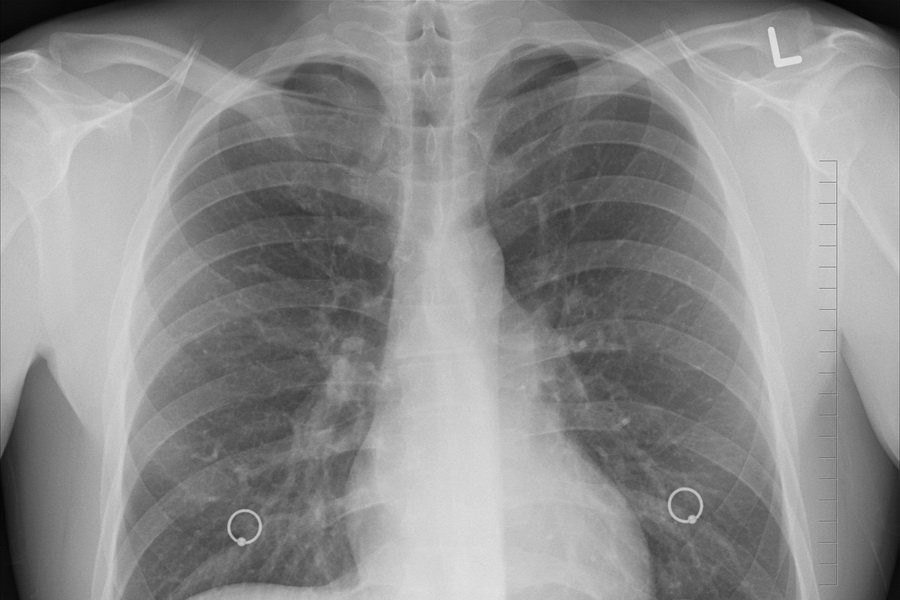

Фото из открытых источников